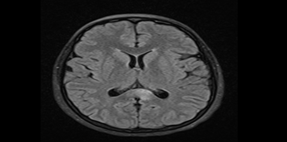

Magnetic Resonance Imaging (MRI) of the Brain shows multiple hyperintense T2 lesions in the corpus callosum with characteristic “snowball” appearance. DWI shows diffusion restriction in the centrum semiovale and parietal lobes, indicative of microinfarcts.

Figure 1. 06-Nov-2023 MRI: FLAIR/T2 shows ill-defined hyperintense lesions in the posterior corpus callosum.